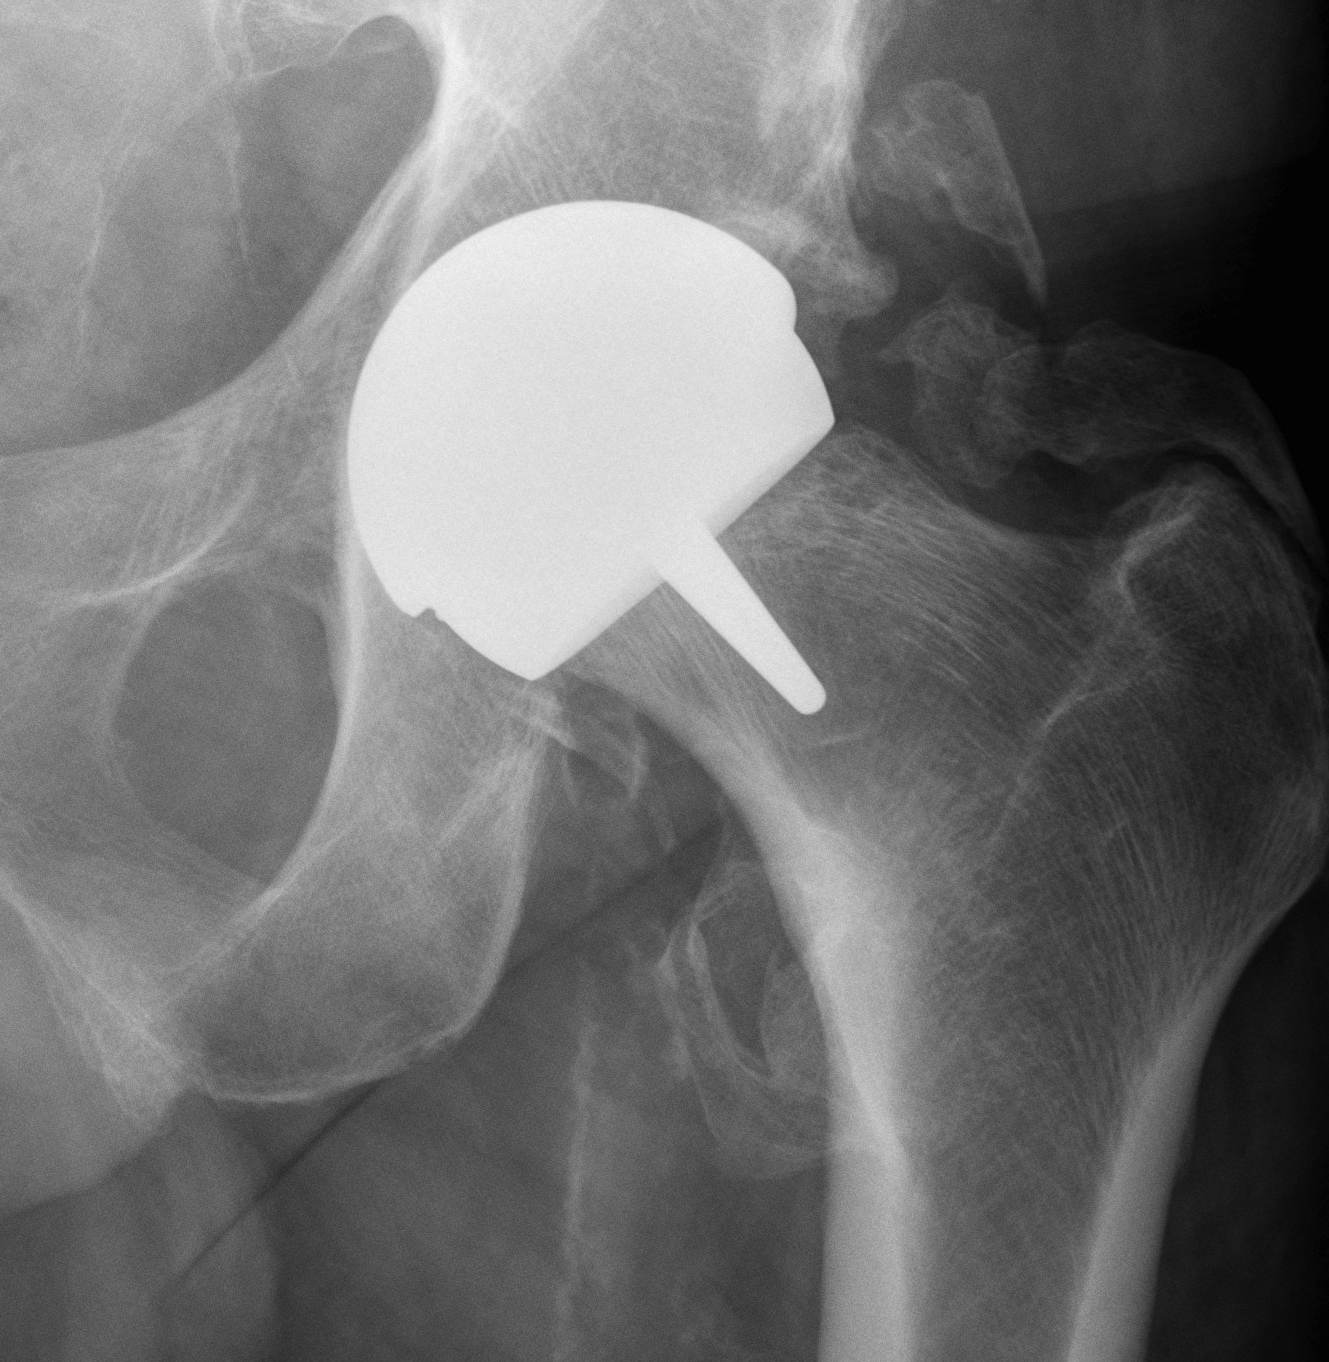

Birmingham hip resurfacing

Concept

Femur - removal of femoral head cartilage and resurfacing with metal

Acetabulum - standard technique

Bearing surface - metal on metal

Birmingham Resurfacing

Smith&Nephew Birmingham Resurfacing PDF